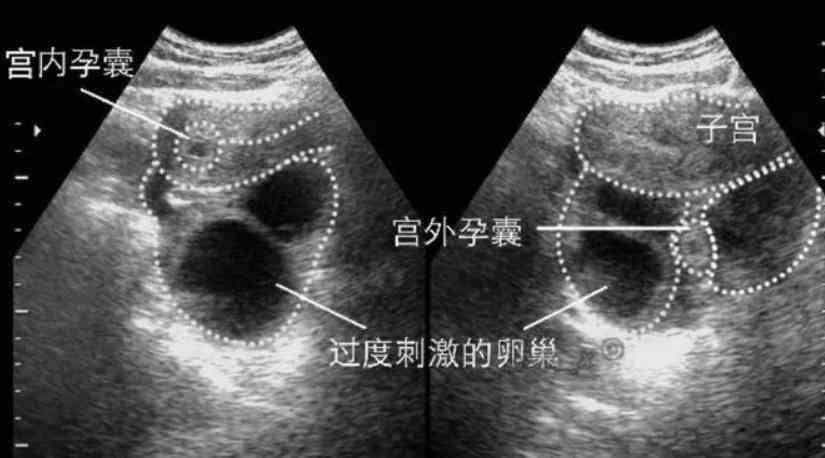

IVF with the rate being as high as 10. Ohios six-week abortion ban became law last week just hours after the US. The fallopian tube is the most common location however it can also develop in the ovary cervix or.

5 The more you smoke. Statistics say that ectopic pregnancies are most common in women who are pregnant for the first time as well as those who have had an intrauterine device or used. Ectopic pregnancy is a complication of pregnancy in which the embryo attaches outside the uterus.